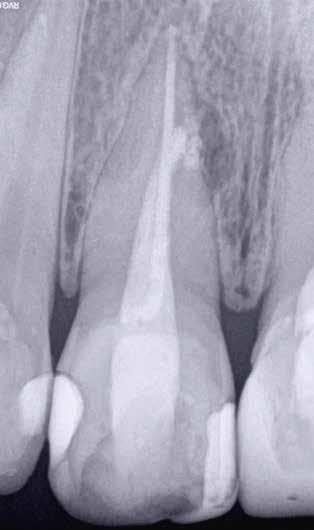

Egy 38 éves nőbeteg a korábban kezelt jobb felső második kisőrlőfogából (1.5) kiinduló mérsékelt fájdalom miatt jelentkezett rendelésünkön. A kórtörténetében jelen panasza szempontjából releváns információ nem szerepelt. A beteg a klinikai vizsgálat során vertikális kopogtatásra enyhe érzékenységet jelzett. A kérdéses fog körül mérhető szondázási mélység és a fogmobilitás fiziológiás volt. Periapicalis röntgenfelvételen egy, a fog gyökércsúcsán túl presszálódott betört gyökérkezelő műszerből származó eszközfragmentumot láttunk (2. a. ábra). A preoperatív CBCT-felvétel a buccalis csontlemez épségét igazolta (2. b-c. ábra). A fog revíziója öt hónappal korábban történt. A már előzőleg gyökérkezelt, gyökértömött, majd revideált 1.5-ös fog esetében a diagnózisunk periodontitis periapicalis symptomatica volt. A periapikális elváltozás kezelése érdekében navigált endodonciai mikrosebészeti beavatkozást végeztünk.

a-m. ábrák: Preoperatív röntgenfelvétel (a) és preoperatív CBCT-felvétel a jobb felső 5-ös (1.5) fogról, sagittalis (b) és axialis (c) nézetek. Az intraorális szkennelés során kapott STL-fájl (d). A 1.5-ös fog navigált endodonciai mikrosebészeti beavatkozásához tervezett sablon (e). A 1.5-ös fog navigált endodonciai mikrosebészeti beavatkozásához nyomtatott sablon (f). Teljes vastagságú mucoperiostealis lebenyt emeltünk (g). A sablont a helyére illesztettük, és a csontablak határait jelöltük (h). A fog gyökerén kívül eső, betört eszköz a 1.5-ös fog periapicalis régiójában (i). Az eltávolított betört eszköz (j). A rezekció, retrográd preparáció és a TotalFill BC RRM Fast Set Putty anyaggal elkészített retrográd gyökértömés utáni röntgenfelvétel (k). A lebenyt varratokkal rögzítettük (l). A kétéves kontroll során készített röntgenfelvétel (m).

gítségével tovább módosítottuk. Az így kapott sebészi sablon egyértelműen meghatározta a periapikális terület eléréséhez szükséges csontablak határait (2. e-f. ábra) Helyi érzéstelenítést követően teljes vastagságú mucoperiostealis lebenyt képeztünk, majd a buccalis csont feltárását követően (2. g. ábra) a sablon segítségével bejelöltük a preparálandó csontablak határait (2. h. ábra). A csontablak kialakítása során Piezotome CUBE LED kézi-darabot alkalmaztunk, majd a leemelését követően a betört eszközt megkerestük (2. i. ábra) és eltávolítottuk (2. j. ábra). A rezekciót ultrahangos megmunkáló fejekkel (ACTEON) végeztük, majd retrográd preparáció következett.

A retrográd gyökértömés elkészítése során TotalFill BC RRM Fast Set Putty-t (FKG) használtunk (2. k. ábra). A lebeny széleit 5/0-s Prolene varratokkal egyesítettük (2. l. ábra). A varratok a műtétet követően 72 órával kerültek eltávolításra. A beteg két évvel később kontrollröntgen készítése céljából érkezett rendelőnkbe. A vizsgálat során a fog tünetmentesnek és funkcióképesnek bizonyult (2. m. ábra).